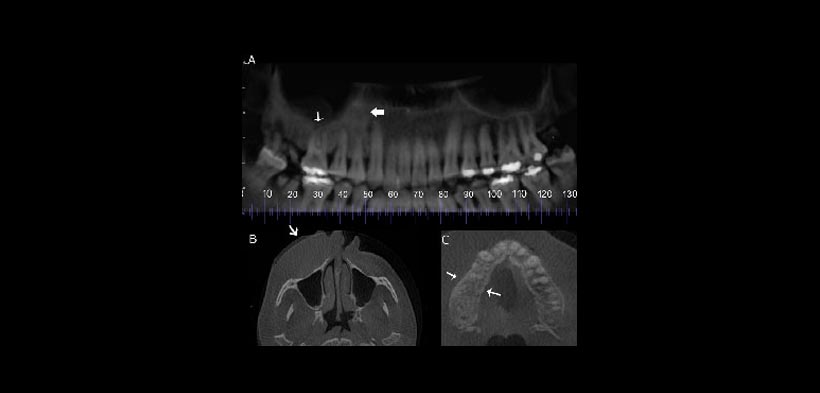

Fig. 2. CBCT reconstrucción panorámicas y vistas axiales. (a) la reconstrucción panorámica CBCT del maxilar que demuestra la ausencia de un piso sinusal bien delineada en el lado derecho (flecha delgada) vs un suelo del seno de apariencia normal bien delineada en el lado izquierdo. También es evidente el ensanchamiento del espacio del ligamento periodontal en el canino superior derecho y la extensión de la esclerosis anterior a los diente cariados (flecha gruesa). (b) vista CBCT axial que demuestra la asimetría del representante de los tejidos blandos. La flecha indica la hinchazón de los tejidos blandos. (c) CBCT vista axial que demuestra la ausencia de la expansión del maxilar derecho y la ausencia de reacción perióstica (flechas) descartando algun proceso infeccioso.